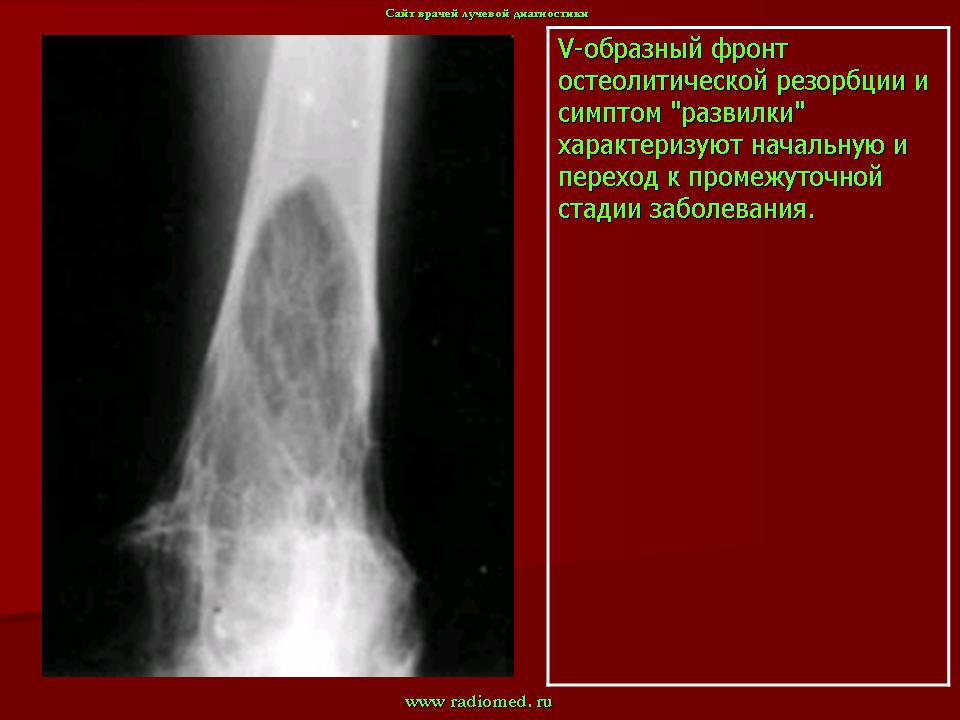

I стадия (литическя) — острая стадия, определяется деструкция кортикального слоя в виде очагов пламени или в форме клина.

II стадия (переходная) – смешанное поражение (остеолиз + склероз).

III стадия (склеротическая) – преобладание склероза с возможной деформацией кости

В монооссальных случаях, частота которых, согласно публикациям, начинается от 10-20% доходя до почти 50%, дифференциальный диагноз может быть гораздо сложнее. В огромном большинстве случаев БП, наличие неоднородных участков костного склероза или остеолиза с искажением трабекулярной архитектуры в сочетании с кортикальным утолщением и фокальным утолщением кости практически патогномоничен для данного заболевания. Бедренная кость является второй наиболее распространенной монооссальной локализацией после таза. В случаях, когда имеется ее дистальное поражение, рентгенологические признаки, характерные для БП, выявляются с меньшей частотой или менее выражены, так что дифференциация с другими процессами, в частности, опухолевыми, может быть затруднена.